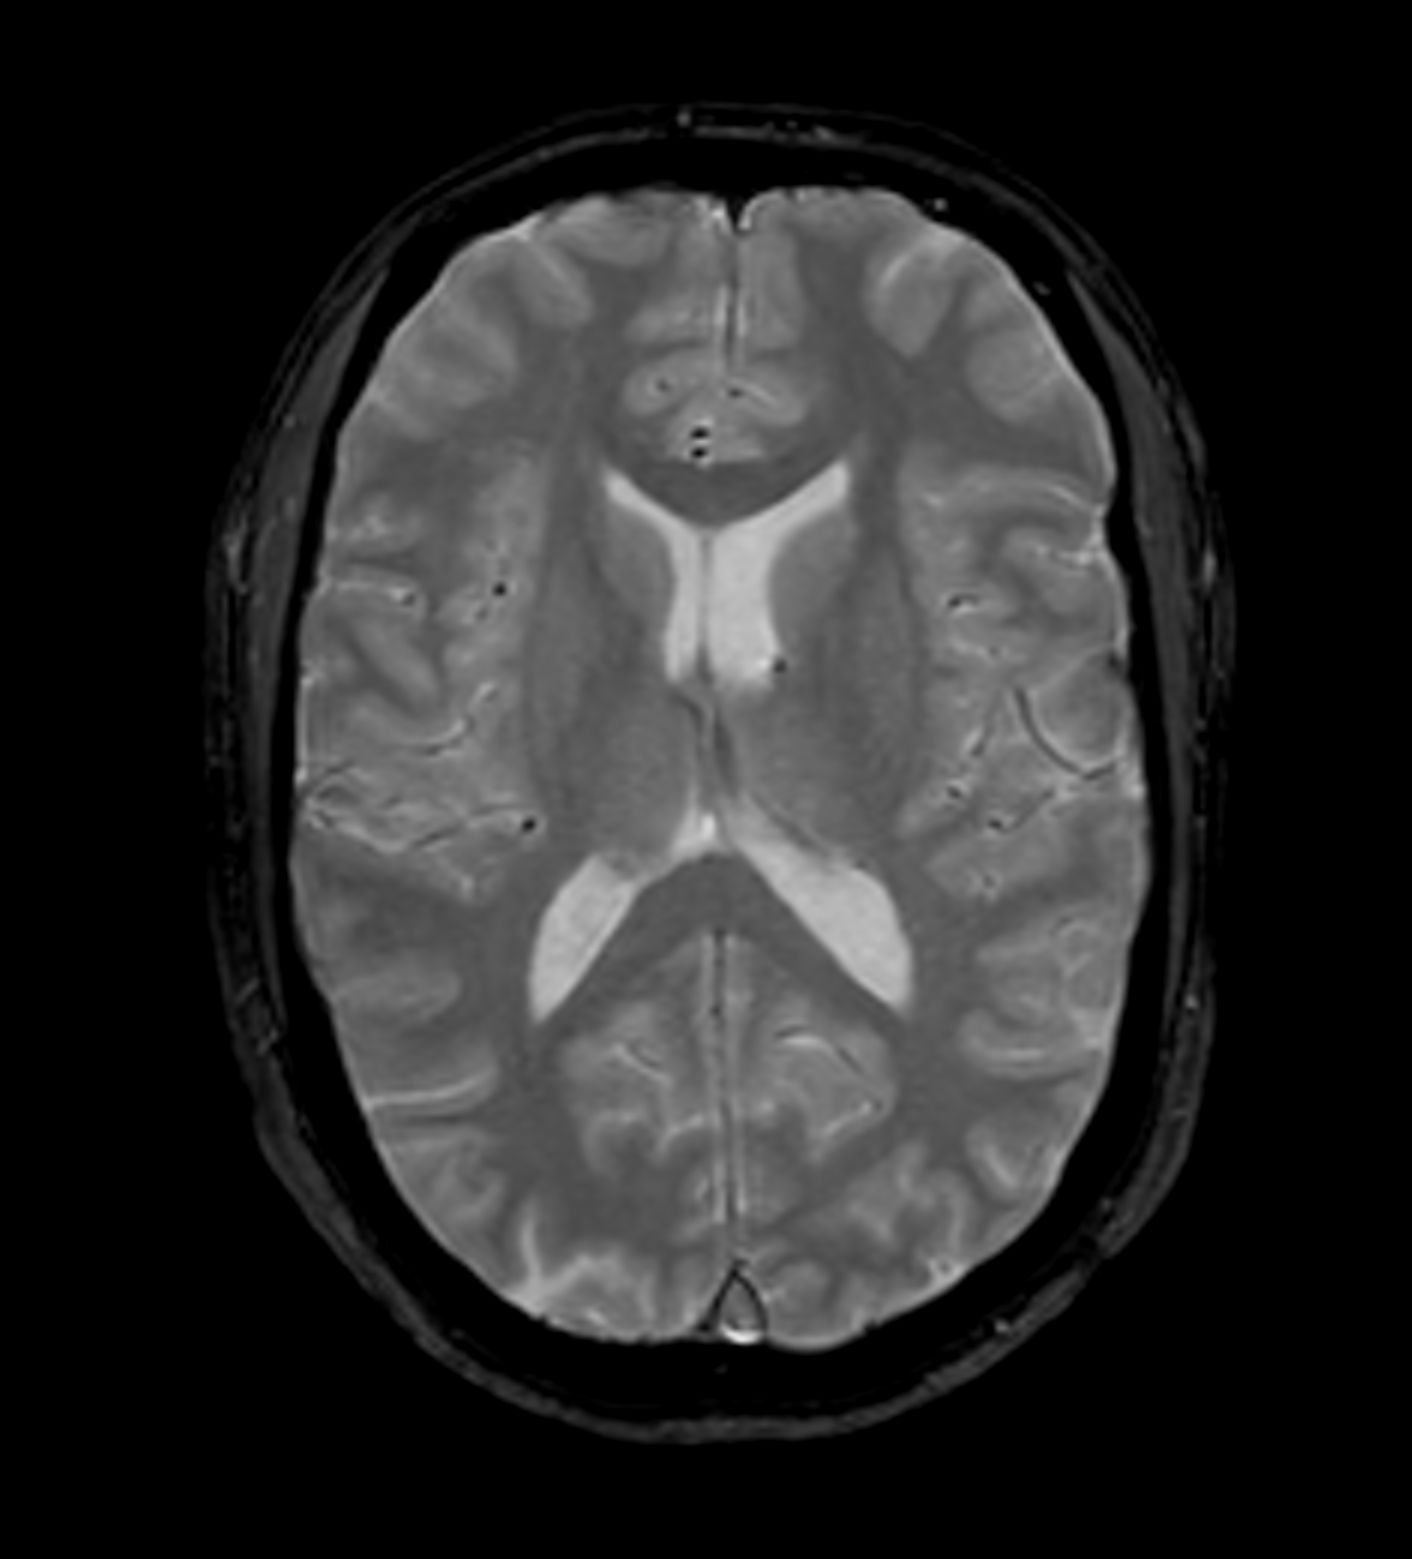

Alzheimer’s Disease Anti-Amyloid Immunotherapies (ARIA) 1.5T

Amyloid clearing medication, such as Aduhelm (Aducanumab) and Leqembi (Lecanemab) have been cleared by the FDA in 2022/2023, to slow down cognitive decline in early-stage Alzheimer’s disease. ASNR-recommendations for AD therapeutic imaging were published in 2022 for eligibility assessment as well as for monitoring for amyloid-related imaging abnormalities. This ExamCard includes ASNR-recommended consensus protocols for imaging of Alzheimer’s Disease Anti-Amyloid Immunotherapies (ARIA). (Cogswell et al., AJNR 2022,43(9)E19-E35;DOI: https://doi.org/10.3174/ajnr.A7586))